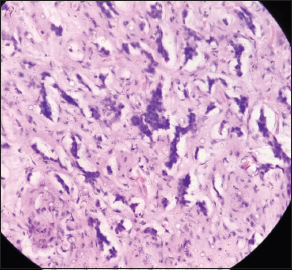

| Figure 3 Esophageal biopsy showing invasive tumor with features of squamoid differentiation (H and E, ×40)